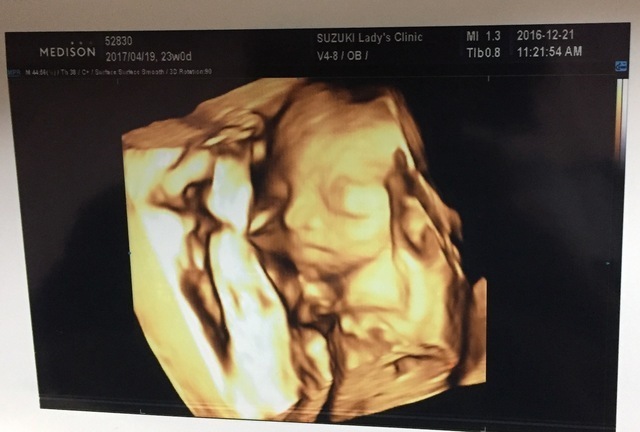

23週0日(23w0d・不明)|ともかりん さん(28歳)

エコー写真撮影時のエピソード:

やっとやっとお顔を見せてくれました。 このエコー写真だけまともなお顔。

先生も何回か挑戦してくれたけど、他は恥ずかしいのか背中やおててだけです。なのでこの1枚が唯一の宝物!恥ずかしいがりやは誰に似たのかな。